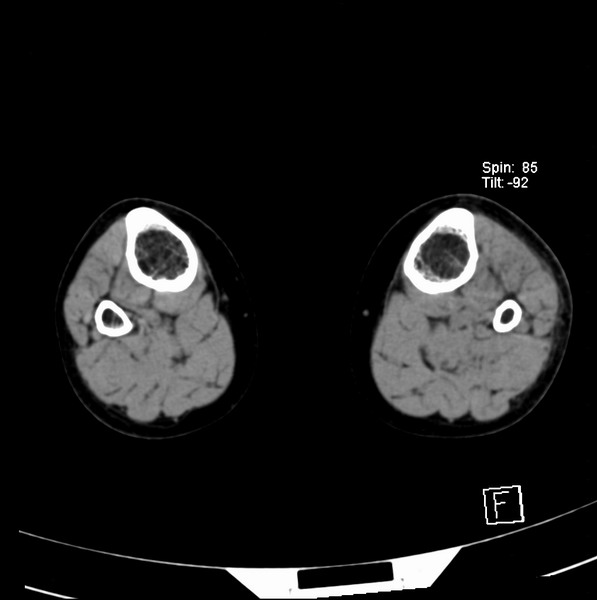

标题: CT21917:右腓骨小头是否骨软骨瘤? [打印本页]

标题: CT21917:右腓骨小头是否骨软骨瘤?

女、43.

不是骨软骨瘤,“牵拽征”,正常变异。有平片吗?

正常变异,“牵拽征”,比目鱼肌牵拽.